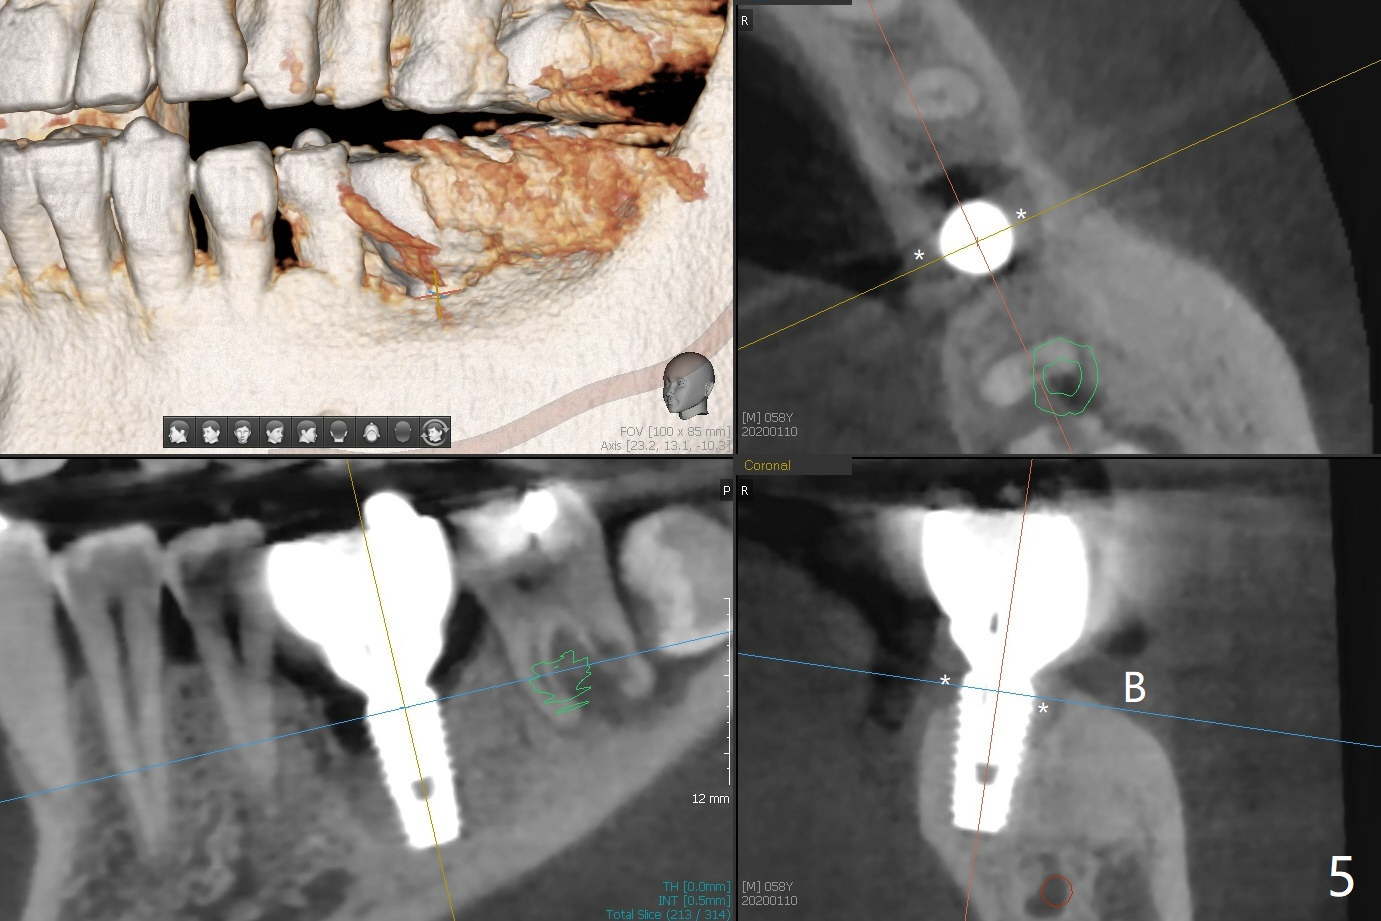

A 58-year-old man appears to have furca lesion or fracture the roots of the tooth #18 three years 5 months post cementation of #19 (Fig.1). In fact the abutment screw gets loose twice even with a buried screw driver. The implant at #18 will be a large tissue-level one (Fig.2). Use a thumb driver to place the implant initially through the metal sleeve for orientation. Although bone resorption mesial to #19 implant looks more severe in panoramic X-ray (Fig.3 *) and the sagittal view of CT (Fig.5) than PA (Fig.1), there is bone (less density) buccal (B) and lingual (Fig.5 *). Bone graft will be conducted at #19 if clinical exam confirms deep pocket the same time of #18 surgery. Distal radiolucency of #18 (Fig.3 *) makes it necessary to extract #17 simultaneously as well. Prepare Titanium brush.